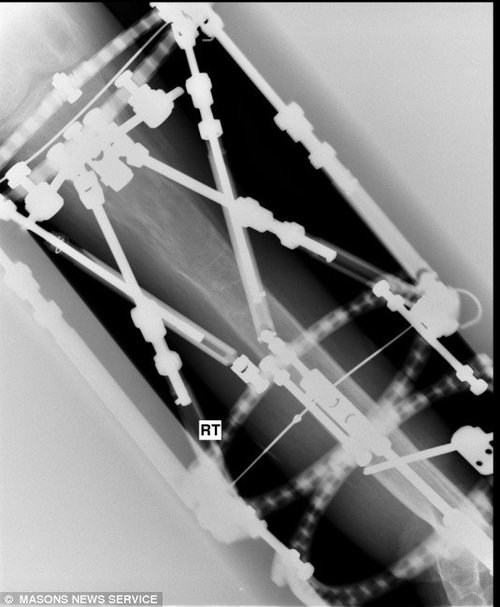

Парень молоток (5 фото)

Мальчик родился с дефектом ноги, ну не росла она. Но он не сдался, аппарат Элизарова сотворил чудо.....